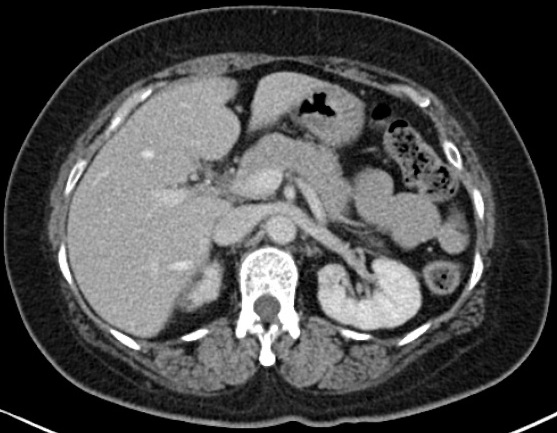

Image radiologique normale du

pancreas en coupe TDM axiale .: Pancreas dans ce cas

est en meme densite des muscles et du

foie |

Une injection de produit de contrast iode

au temps arteriele pancreatique ( 40-45s apres

injection ) se donne de image de rehaussement maxima

du parenchyme pancreatique . A ce temps le panreas

est hyperdense que le foie et les autres organes |